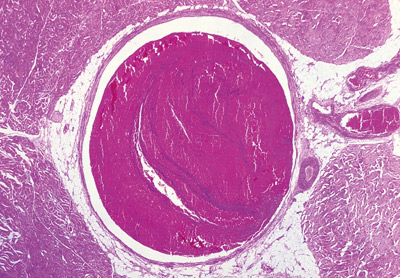

Gravide har økt risiko for venøs trombose. Faktor V Leiden-mutasjonen og protrombin G20210A-mutasjonen er de to vanligste genetiske risikofaktorene for venøs trombose. Vi har undersøkt om disse genetiske variantene øker risikoen for svangerskapsrelatert venøs trombose og om det ville være hensiktsmessig å analysere dem hos gravide (1).

Studien omfattet 377 155 kvinner som fødte i perioden 1990 – 2003, der 559 kvinner fikk venøs trombose under svangerskapet eller innen tre måneder etter fødselen. Kontrollpersoner var 1 229 kvinner som fødte uten å få venøs trombose. Faktor V Leiden-mutasjonen og protrombin G20210A-mutasjonen ble analysert hos 313 pasienter og 353 kontrollkvinner.

Ni kvinner var homozygote for en av de genetiske variantene, og alle fikk venøs trombose. Heterozygote for faktor V Leiden hadde fem ganger økt risiko for venøs trombose, mens de som var heterozygote for protrombin G20210A-mutasjonen hadde ni ganger økt risiko. Basert på disse tallene hadde gravide som var heterozygote for faktor V Leiden en sannsynlighet for venøs trombose på 5,4 per 1 000. Tilsvarende tall for protrombin G20210A-mutasjonen var 9,4 per 1 000.

Funnene betyr at ved masseundersøkelse av gravide kvinner for disse to genetiske risikofaktorene må man teste 2 015 gravide og gi 157 tromboseprofylakse for å forebygge én svangerskapsrelatert venøs trombose. Selv om begge mutasjonene øker risikoen for svangerskapsrelatert venøs trombose, er det likevel så mange bærere av disse genvariantene som ikke får venøs trombose at masseundersøkelse er hensiktsløst.